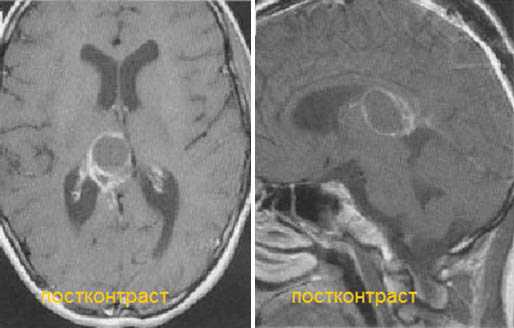

Диагностика: МРТ с контрастным усилением — стандартное исследование при опухолях этой локализации. При пинеоцитоме обнаруживают небольших размеров округлое образование в пинеальной области, с чёткими границами, активно и гомогенно накапливающее контраст и вызывающее компрессию пластинки четверохолмия. Для пинеобластомы характерны все признаки злокачественной быстро прогрессирующей опухоли (инфильтративный характер роста, гетерогенный сигнал с признаками некроза и кровоизлияний, большие размеры, субарахноидальные метастазы).

Пинеоцитома. МРТ в режиме Т2 и Т1 выявляется солидного строения опухоль задних отделов III желудочка мозга. На фоне в/в контрастирования определяется выраженный и достаточно гомогенный характер контрастирования опухоли.